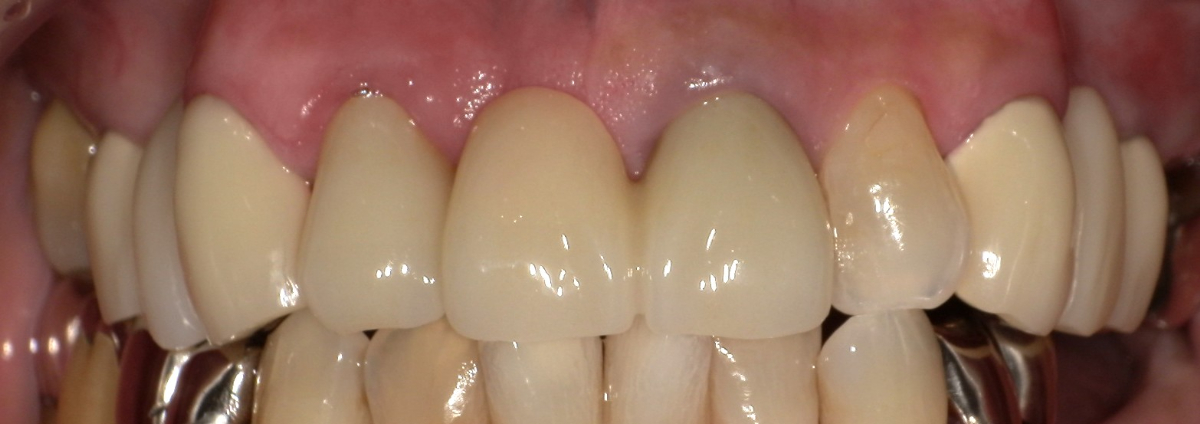

<治療前>

<治療後>

主訴:上の前歯の色が気になる、もっと白くしたい

上部構造:すべてジルコニアセラミック

費用:¥1,320,000

治療期間:2ヶ月

副作用・リスク:特に前歯部は、色合わせのために何度か作り替えが必要な場合があります。歯周病、う蝕、根の治療が必要な場合はさらに時間がかかります。